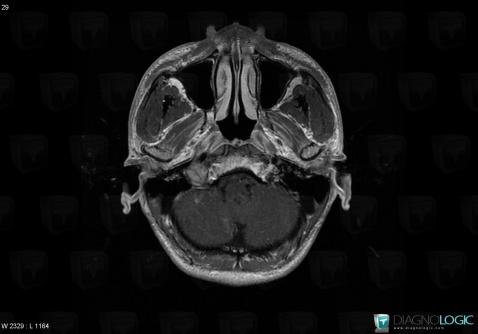

Schwannome, Espaces peri cérébraux infratentoriels, Autres nerfs craniens, IRM

Voici les informations spécifiques à l'image clé ci dessus:

- Diagnostic Schwannome, Localisation(s) Autres nerfs craniens, comportant les gammes Lésion des nerfs craniensEspaces peri cérébraux infratentoriels, comportant les gammes Lésion extra axiale infra tentorielleFosse postérieure, comportant les gammes Lésion infratentorielle en hypersignal T2 ou FLAIR